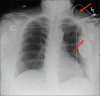

Twiddler's syndrome refers to malfunction of pacemaker or implantable cardioverter-defibrillator (ICD) resulting from deliberate or unintentional twisting of pulse generator in device pocket, resulting in lead dislodgment. We report a case of a 65-year-old woman with multiple ICD shocks and antitachycardia pacing events on device interrogation, while she was unaware of the ICD discharges. Twiddler's syndrome is rare and mostly occurs in obese or elderly because of loose subcutaneous tissue allowing pulse generator to rotate in its pocket. It can be prevented by patient education against hand manipulating the generator. Smaller device pocket or suturing generator to fascia can also prevent future episodes.